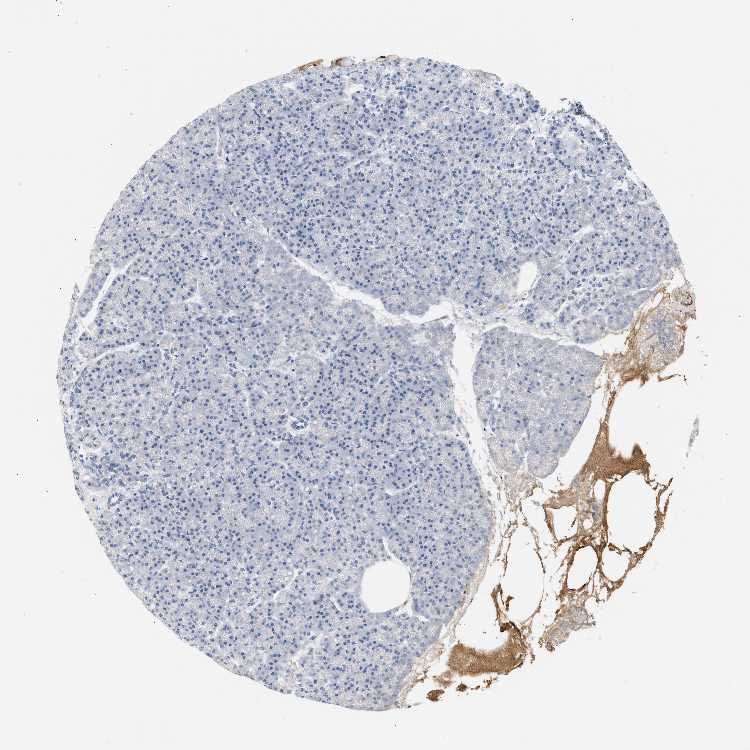

PANCREAS - Antibody stainingi

Antibody staining in the annotated cell types in the current human tissue is reported as not detected, low, medium, or high, based on conventional immunohistochemistry profiling in selected tissues. This score is based on the combination of the staining intensity and fraction of stained cells.

Each image is clickable and will lead to virtual microscopy that enables deeper exploration of all samples and also displays staining intensity scores, fraction scores and subcellular localization as well as patient and tissue information for each sample.

Antibody HPA038922Antibody HPA049176Antibody HPA053326Antibody CAB016385Antibody CAB016769

Exocrine glandular cells Not detectedNot detectedNot detectedNot detectedNot detected

Pancreatic endocrine cells Not detectedNot detectedNot detectedNot detectedNot detected